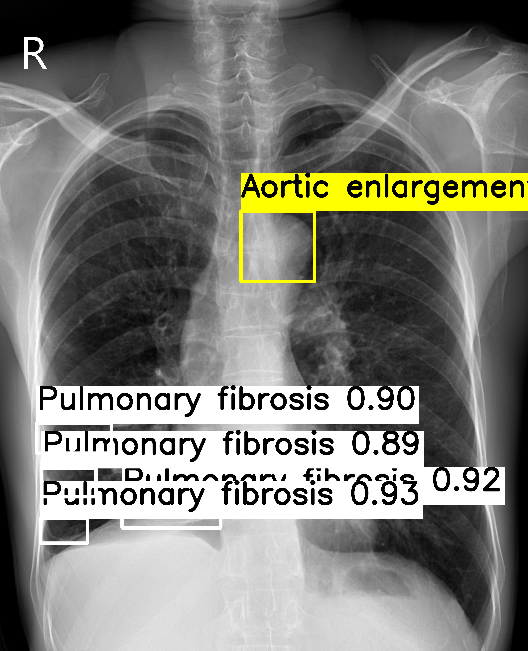

VinDR-CXR

Comparison of aggregated labels on the VinDR-CXR chest radiograph dataset. For WBF-EARL, the number beside the class label is the annotators' level of agreement while for Crowd R-CNN and BDC, the number indicates the class probability.

BDC (ours)